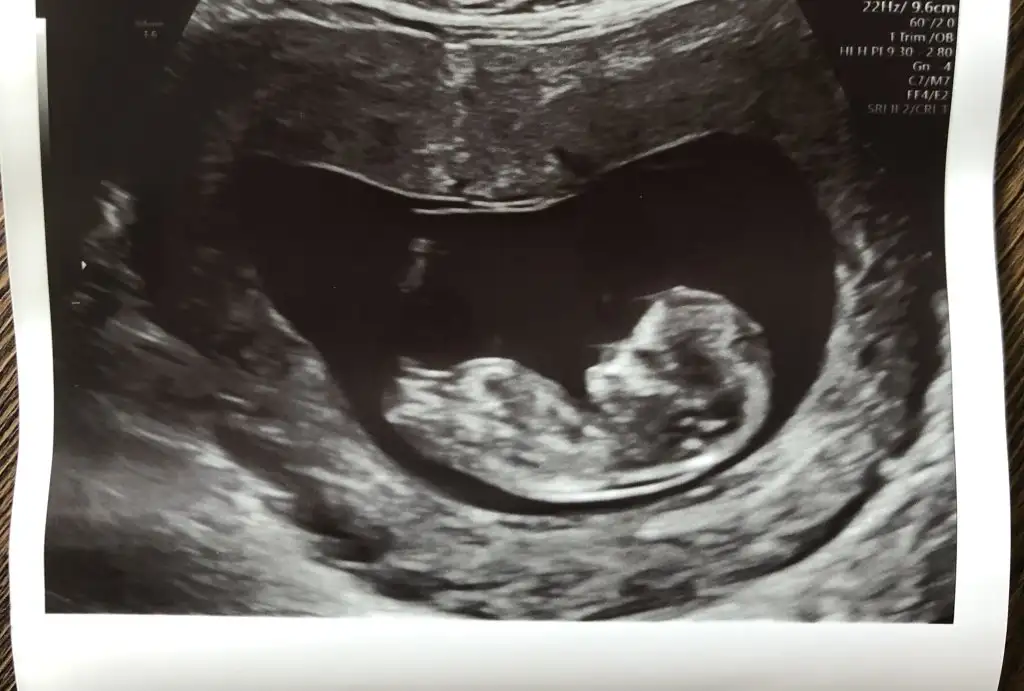

Atmıştım kuzum tekrar atayım

• IMG-20220907-WA0000.webp

15,5 KB · Görüntüleme: 65